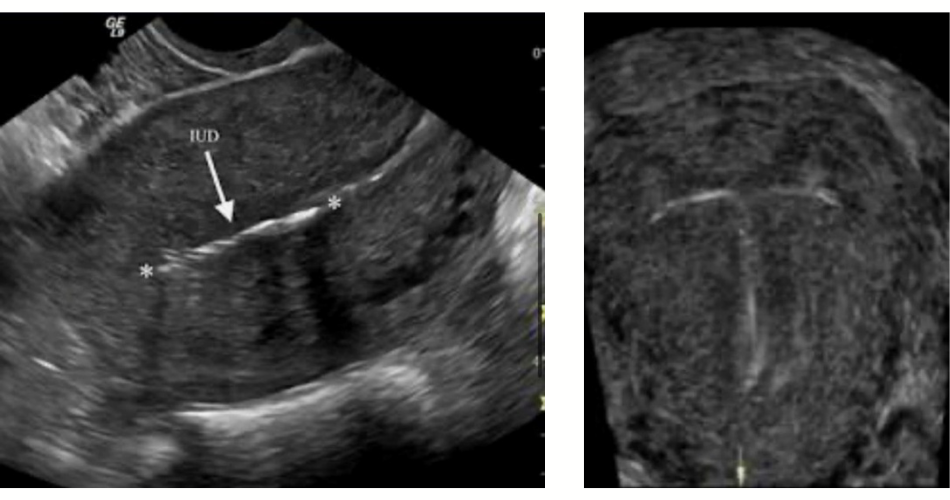

Část prezentace se věnovala IUD v ultrazvukovém obraze, viditelnosti jednotlivých typů a ultrazvukovému nálezu při nesprávném uložení tělíska.

Třetí kazuistika popsala případ ektopicky uloženého IUS v dutině břišní po dvou letech užívání metody, následnou diagnostiku uložení, laparoskopické odstranění a opětovné zavedení IUS na přání pacientky po hysteroskopické kontrole zhojení děložní stěny.